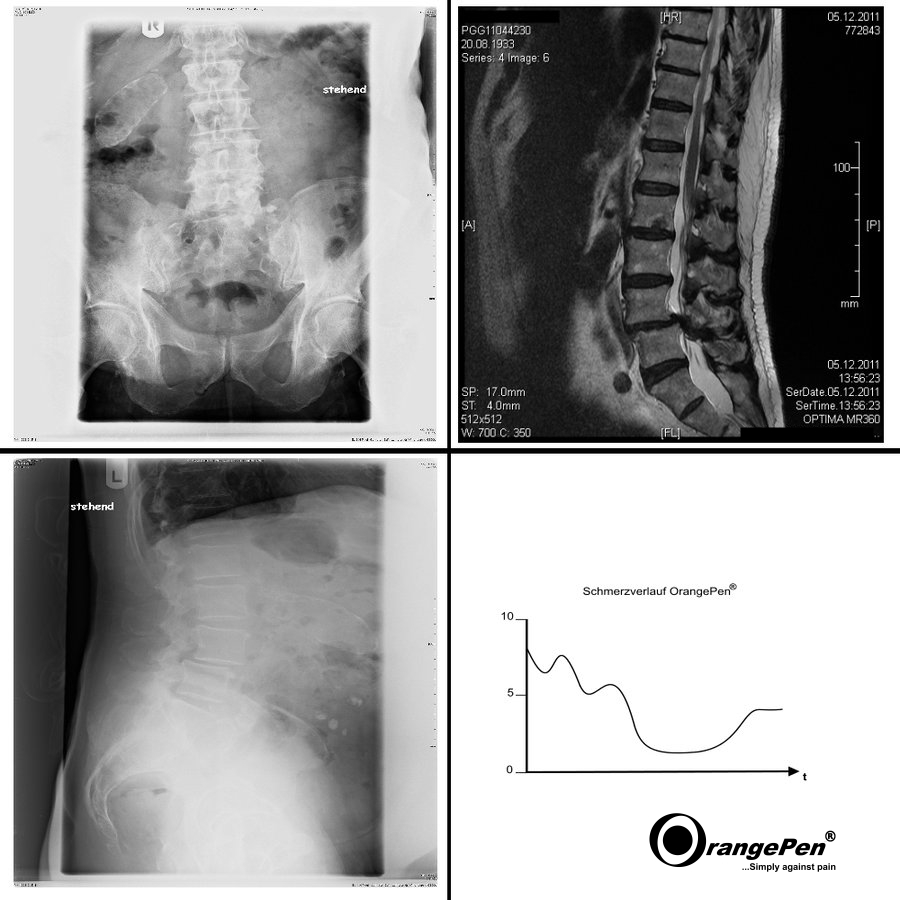

Back with vertebral anomaly

Back with vertebral anomaly treated with OrangePen®

After the second treatment the pain symptoms improved significantly. After 5 treatments, further occurring pain could be treated sporadically. The first treatment took place in 2012 and the patient had not felt any worsening of the symptoms since then.

Surgery and painkillers are still not required today. Patient has clearly more quality of life.